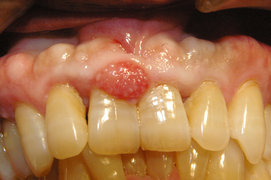

歯肉に限局的にできる腫瘤で『エプーリス』

歯肉に限局的にできる腫瘤で『エプーリス』ってきいたことありますか? エプーリスは歯肉に発生する良性の限局性腫瘍です。エプーリスと癌の違いとしては癌のような悪性腫瘍とは異なり、エプーリスは良性の腫瘤(しゅりゅう)の総称で歯 […]